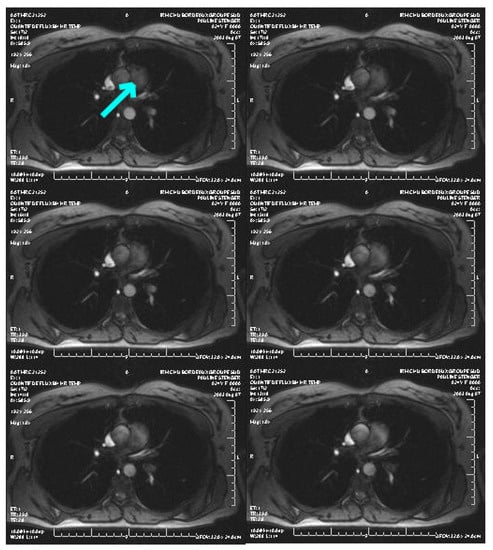

3.3. Applications to Medical Imaging

Here, we apply our method to 2D medical images, the goal being to outline the cross-sectional area of a great thoracic vessel, namely the main pulmonary artery, in order to non-invasively assess pulmonary arterial hypertension. Figure 9 refers to a slice set perpendicularly to the MPA axis (arrow) of a 78 years old patient, who was suspected of pulmonary arterial hypertension, suffering from breathlessness. The presented magnitude image was acquired from a velocity encoded sequence (Venc = 1.5 m/s), during a 5 min time duration, with a 30 ms temporal resolution (1T Magnetom Expert imager; Siemens; Germany). The image quality is moderate, and in particular the vessel wall is irregular around the arrow, that is, not anatomically possible, and therefore an interpolation in the outlining by the physician is needed.

Since the lack of annotated data is one of the most common limitations encountered in many deep learning approaches like the ones we will study in this subsection, deep leaning approaches are not suitable (at least for now!) for our considered applications.

Figure 9. Example of an image sequence (courtesy of CHU Bordeaux, France). The arrow shows the pulmonary artery to segment.